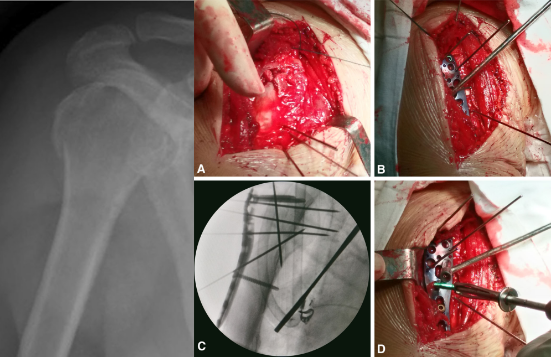

肱骨大结节骨折 ORIF,术前 X 线片显示肱骨大结节骨折情况;术中暴露肱

肱骨大结节骨折 ORIF,术前 X 线片显示肱骨大结节骨折情况;术中暴露肱